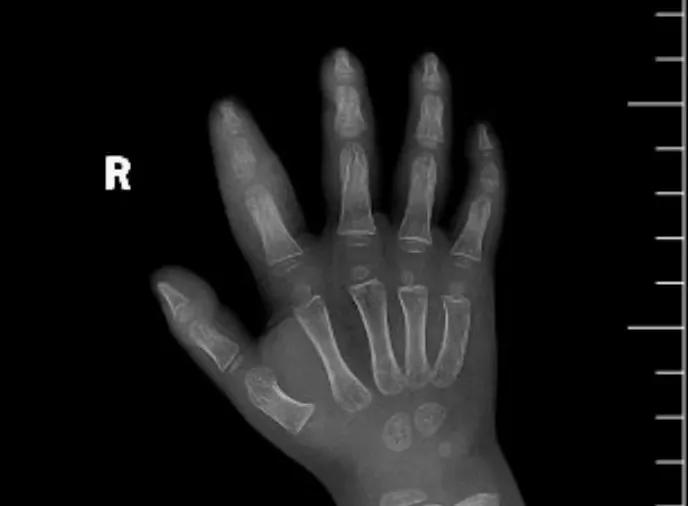

近日,市二院顯微外科接診一名3歲半的小患者,被玉米葉割傷右食指,因家長(zhǎng)疏忽大意,導(dǎo)致一個(gè)小小的傷口竟然發(fā)展成了骨髓炎。來院時(shí)患兒右食指腫脹明顯,既不能伸也不能彎,皮膚發(fā)燙,疼得哇哇大哭。

第三天開始,月月哭鬧不止,一直說手疼,怎么哄也不行,于是在當(dāng)?shù)蒯t(yī)院治療了10來天,然而月月的手指依然腫得像個(gè)胡蘿卜,疼痛感依然存在。此時(shí),月月的媽媽才覺得事情不大對(duì)勁,于是經(jīng)過打聽,慕名來到市二院顯微外科。入院后,經(jīng)檢查發(fā)現(xiàn),月月的右食指骨質(zhì)有侵蝕,骨骺有缺損,甚至?xí)绊懸院笫种傅陌l(fā)育。聽到這個(gè)消息,月月媽媽感覺心都揪住了。

隨后,經(jīng)顯微外科團(tuán)隊(duì)充分的討論,制定了科學(xué)細(xì)致的治療方案,為月月做了感染灶清除及手指的開放引流,并留取了標(biāo)本做細(xì)菌培養(yǎng),為進(jìn)一步的合理用藥提供依據(jù)。經(jīng)過兩周的治療,月月的手指終于順利消腫愈合,并且手指功能活動(dòng)良好。說起這一個(gè)多月的煎熬,月月媽媽不禁落淚,但總算是治愈了,笑容又重新回到她們一家的臉上。